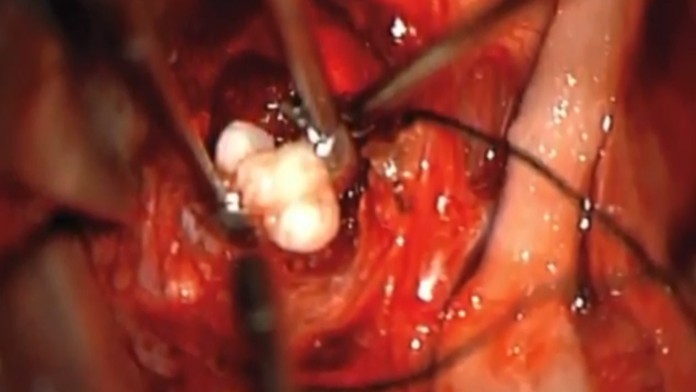

Chlapčeka operovali a v nádore našli niečo veľmi vzácne. Vyrastali z neho zuby. „Zuby v akomkoľvek druhu nádoru v mozgu teda nevidíme každý deň. A v kraniofaryngióme už vôbec," povedal neurochirurg Narlin Beaty, ktorý operoval. Podľa Metro.co.uk je už chlapček v poriadku a je zdravý.